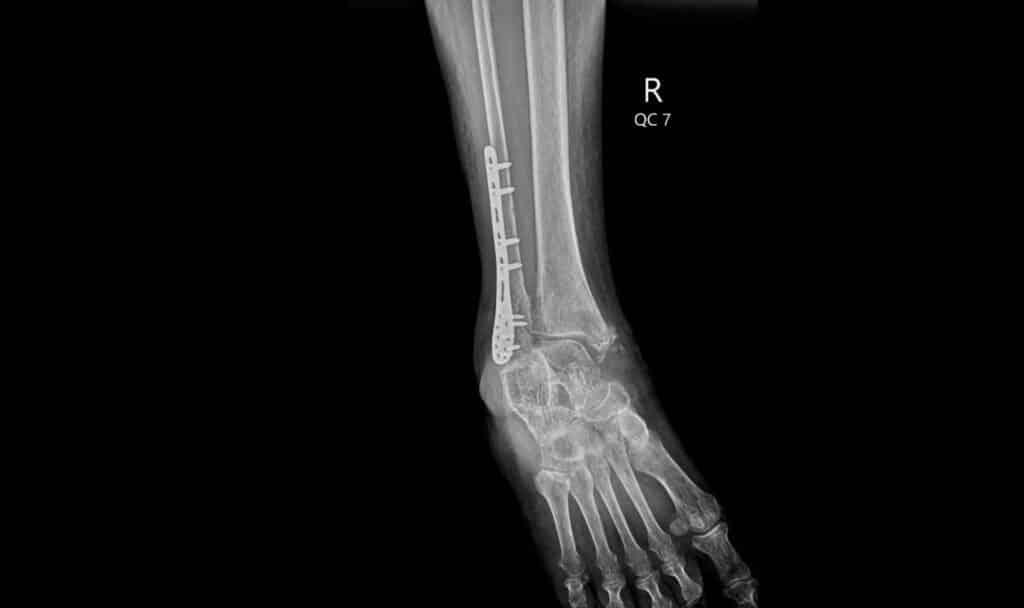

Surgery is more likely if the ankle joint is out of place, if multiple bones are broken, or if ligaments are severely damaged. The goal is to restore normal alignment of the joint and keep the bones steady while they heal.

During surgery, metal plates, screws, or other implants are used to hold the bones in a normal position while they heal. These devices may stay in place permanently unless they cause problems later.